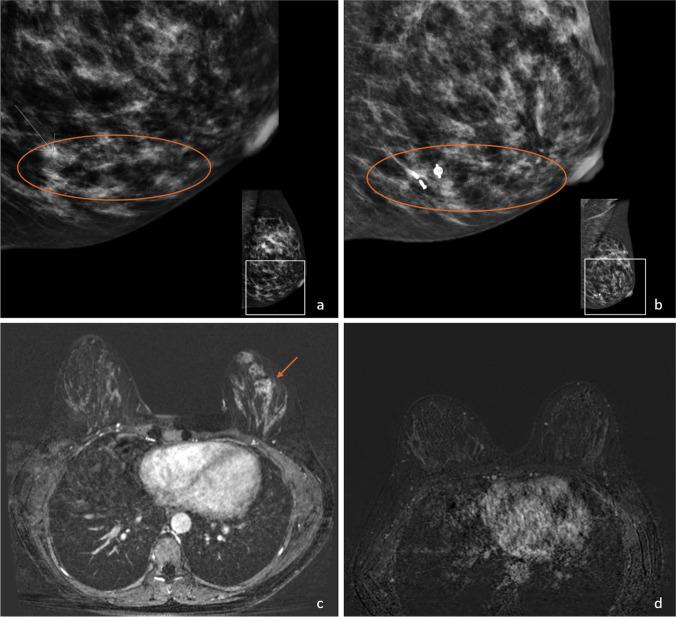

Thirty-one studies were included. Calcifications on mammography are related to DCIS, but can persist despite complete response of DCIS. In 20 breast MRI studies, an average of 57% of residual DCIS showed enhancement. A meta-analysis of 17 breast MRI studies confirmed higher pooled sensitivity (0.86 versus 0.82) and lower pooled specificity (0.61 versus 0.68) for detection of residual disease when DCIS is considered pCR (ypT0/is). Three CEM studies suggest the potential benefit of simultaneous evaluation of calcifications and enhancement.

Calcifications on mammography can remain despite complete response of DCIS, and residual DCIS does not always show enhancement on breast MRI and CEM. Moreover, pCR definition effects diagnostic performance of breast MRI. Given the lack of evidence on imaging findings of response of the DCIS component to NST, further research is demanded.

• Ductal carcinoma in situ has shown to be responsive to neoadjuvant systemic therapy, but imaging studies mainly focus on response of the invasive tumour. • The 31 included studies demonstrate that after neoadjuvant systemic therapy, calcifications on mammography can remain despite complete response of DCIS and residual DCIS does not always show enhancement on MRI and contrast-enhanced mammography. • The definition of pCR has impact on the diagnostic performance of MRI in detecting residual disease, and when DCIS is considered pCR, pooled sensitivity was slightly higher and pooled specificity slightly lower.

共纳入 31 项研究。乳腺钼靶上的钙化与 DCIS 相关,但即使 DCIS 完全缓解,钙化也可能持续存在。在 20 项乳腺 MRI 研究中,平均有 57%的残留 DCIS 显示增强。17 项乳腺 MRI 研究的荟萃分析证实,当将 DCIS 视为 pCR (ypT0/is) 时,检测残留疾病的汇总敏感性(0.86 与 0.82)更高,汇总特异性(0.61 与 0.68)更低。三项 CEM 研究表明同时评估钙化和增强的潜在益处。

尽管 DCIS 完全缓解,但乳腺钼靶上的钙化仍可能存在,并且残留的 DCIS 并不总是在乳腺 MRI 和 CEM 上显示增强。此外,pCR 定义会影响 MRI 检测残留疾病的诊断性能。鉴于缺乏关于 DCIS 成分对 NST 反应的影像学表现的证据,需要进一步研究。

• 纳入的 31 项研究表明,在新辅助全身治疗后,即使 DCIS 完全缓解,乳腺钼靶上的钙化仍可能存在,并且残留的 DCIS 并不总是在 MRI 和对比增强乳腺摄影上显示增强。